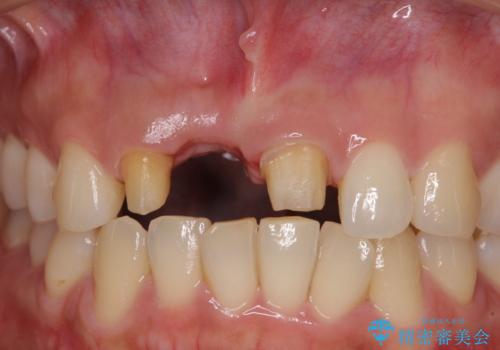

- 仮歯のまま前歯を放置しているとのことで来院された患者様です。

目視で確認できるほどしっかりとした破折が認められ、抜歯が必要と判断されました。

抜歯後は歯肉が痩せてしまうため、歯肉移植を行って歯肉の形態を改善した後、オールセラミックブリッジにて補綴することとしました。

歯肉移植により歯肉ラインや歯の形態を整えることができ、ブリッジによる補綴としたことで舞えば全体の色調を整えることができました。